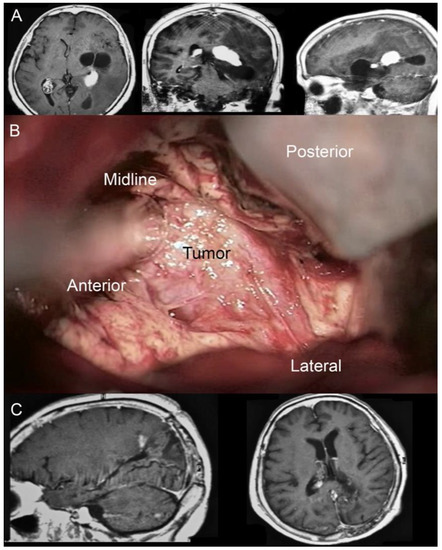

- Illustrative case n.2 (Case n.4 in the table, Figure 5)

Figure 5. (A) Pre-operative MRI documenting the presence of a lesion partially involving the left atrial cavity of the lateral ventricle. (B) Three-quarter prone position for the IITA. (C) Immediate post-operative MRI (T1 sequence with cm) control documenting the complete resection of the lesion and the rehabilitation of the atrial cavity. (D) Immediate post-operative MRI (T2 sequence). Note the absence of post-surgical brain edema. (E) One month post-operative neuological evaluation and surgical linear incision aspect.

A 35-year-old man with a history of melanoma came to our attention because of a drug-resistant headache and aphasia. A brain MRI was performed documenting the presence of a left-sided solid lesion enhancing after the administration of mc partially involving the atrial cavity of the lateral ventricle. The total body CT scan excluded the presence of other metastases. The patient underwent surgical removal through IITA.

Immediately, a post-operative MRI was performed, documenting the complete removal of the lesion. T2 weighted sequences excluded the presence of post-surgical brain edema.

The post-operative course was favorable. His aphasia was remitted, as well as his headache. The patient was discharged on the fifth post-operative day.